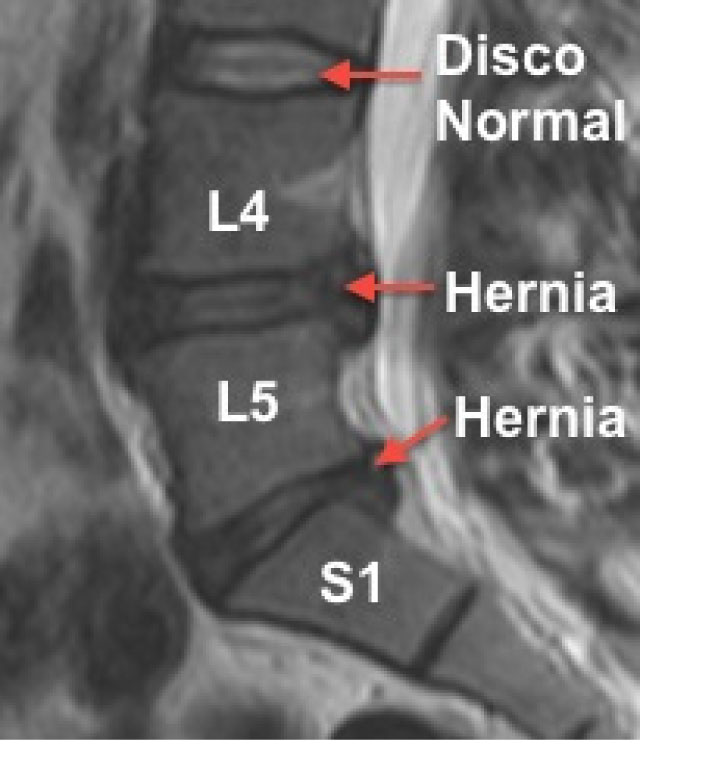

Las lesiones más comunes ocurren en los niveles L4-L5 y L5-S1, donde la columna soporta la mayor carga. El dolor suele aparecer cuando el disco pierde altura, se desplaza (protusión) o se rompe (hérnia). Y el verdadero problema surge cuando:

Y un claro ejemplo lo encontramos en el famoso Meta-análisis de Brinjikji (33 estudios que incluían a 3.110 personas), donde pasamos de ver la hernia como una «lesión catastrófica» a verla como «arrugas internas» propias de la edad. Estas lesiones no guardan relación directa con el dolor.